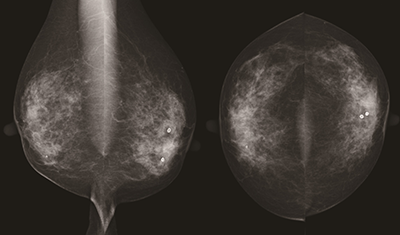

ビューアはトモシンセシス画像の高速表示はもとより,画像比較なども軽快に行うことができる多くの機能を実装しています。所見レポートもマンモグラフィ・エコーの併用検診に対応し,その他にも多くの新しい機能が追加されました。

・乳腺画像診断ワークステーション「mammodite」

高速な画像表示,直感的な操作感によりストレスフリーな読影環境を実現する画像ビューア,簡単操作で詳細な所見を作成できる所見レポーティングシステムを兼ね備える卓越した乳腺画像診断ワークステーションです。